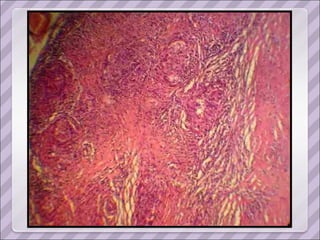

APP Sarcoidosis torácica  (1993, dx por biopsia ganglionar del mediastino. Estadio II) Compromiso cutáneo (eritema nodoso recurrente y refractario en MMII), ocular (uveítis) y del SNP ( mononeuropatía múltiple). Tratamiento prolongado con corticoides y azatioprina.  Cushing exógeno Diabetes inducida por esteroides Serología positiva para Hepatitis C en 2006